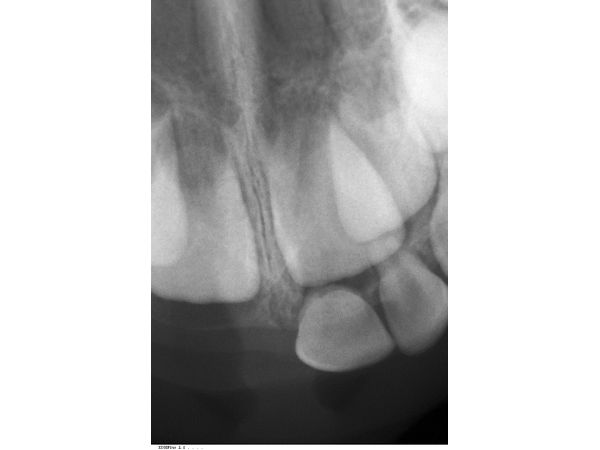

По результатам прицельной рентгенограммы, в лунках правых верхних резцов корней не было. Она также показала перелом в верхушечной трети корня левого центрального резца.

Перелом корня зуба 61, полный вывих (экзартикуляция) зубов 51 и 52.